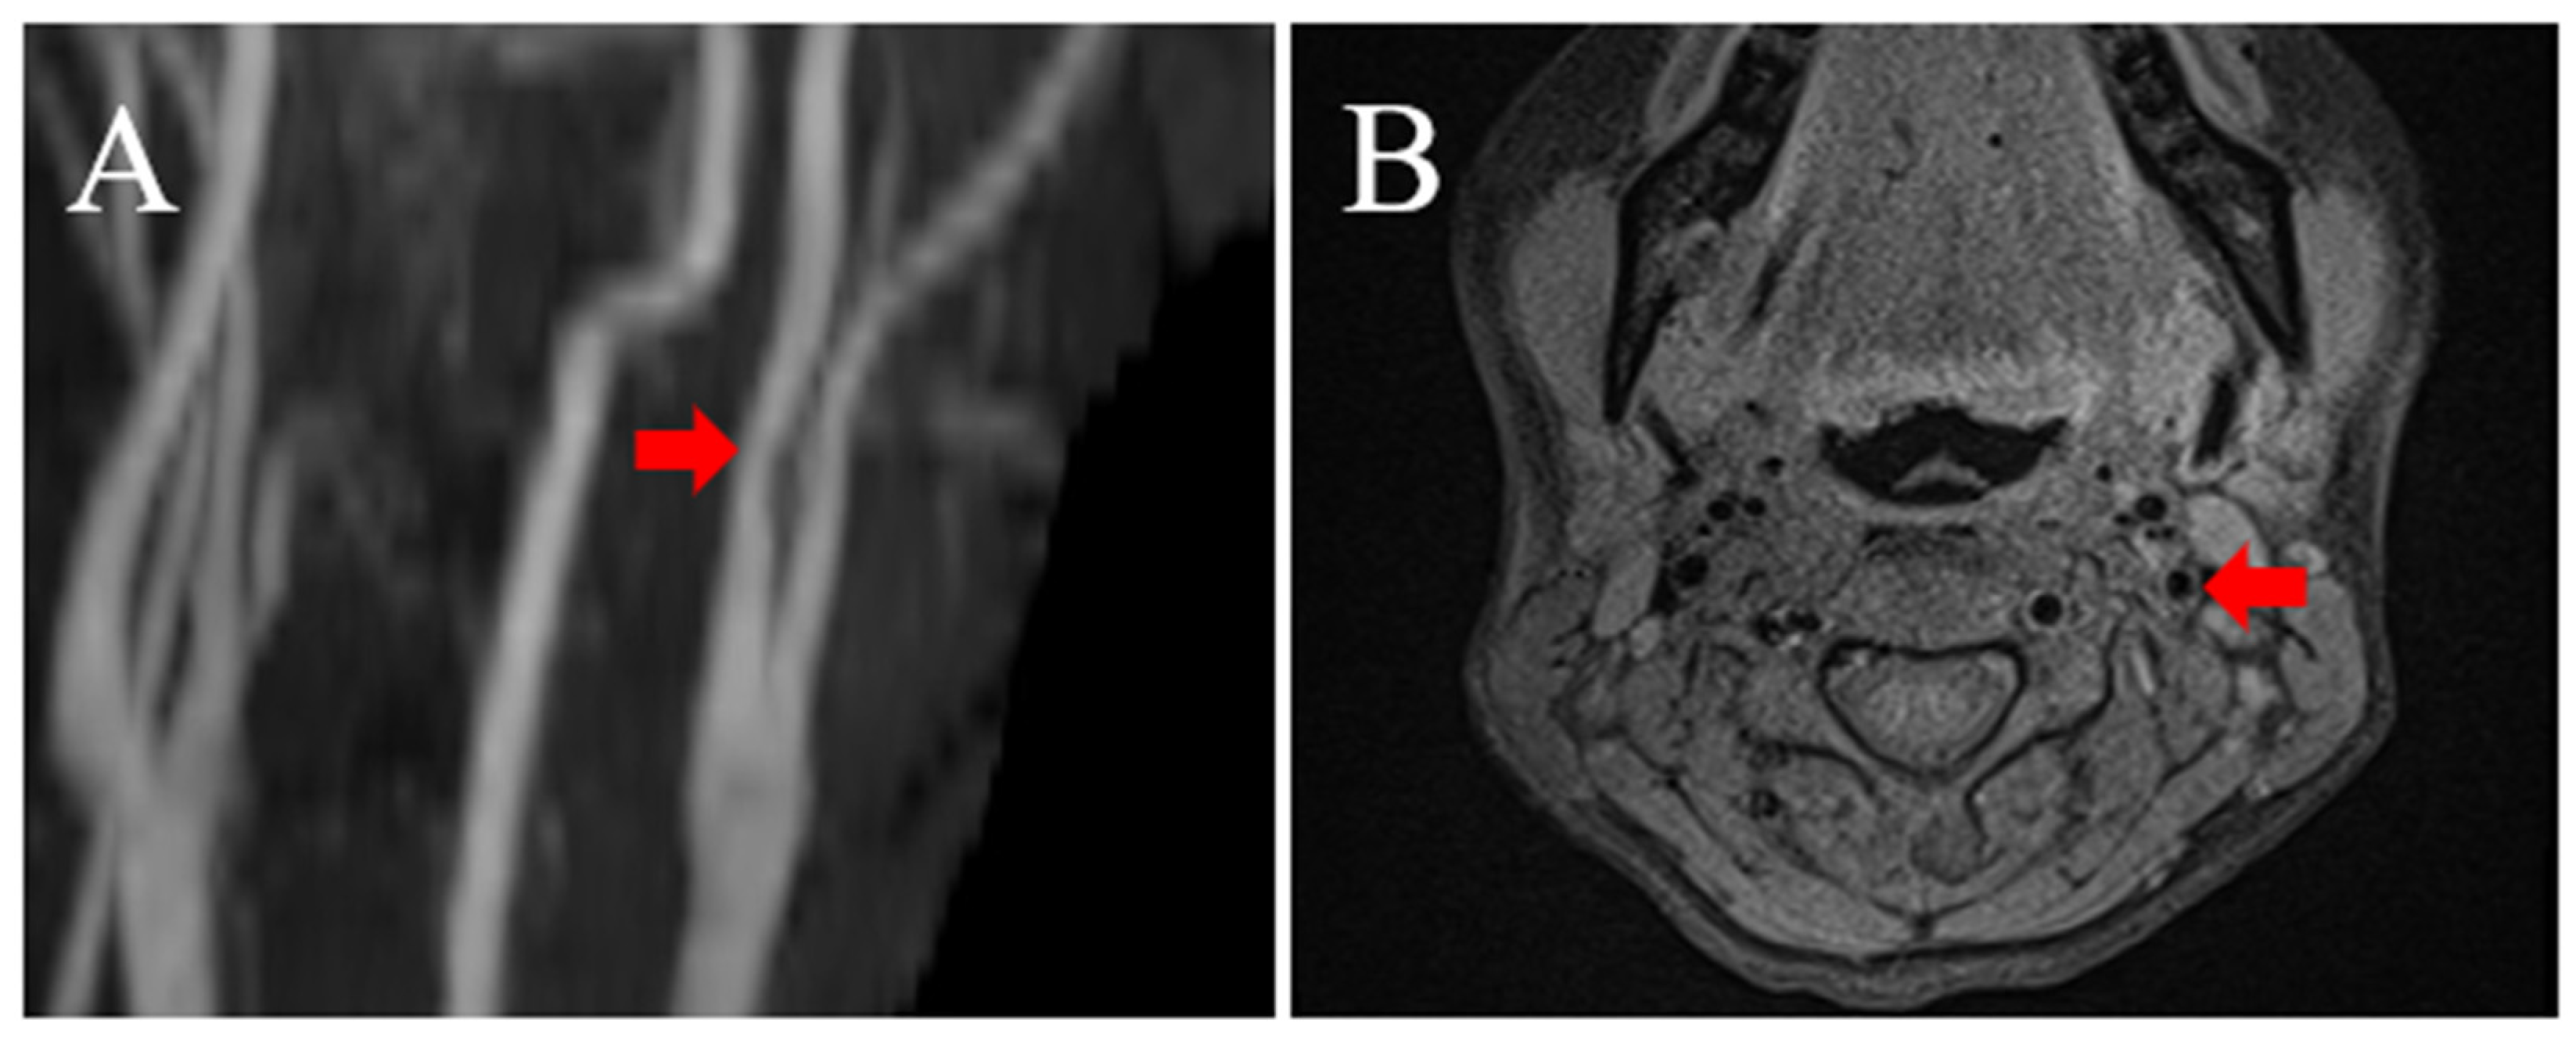

2. Illustrative Case